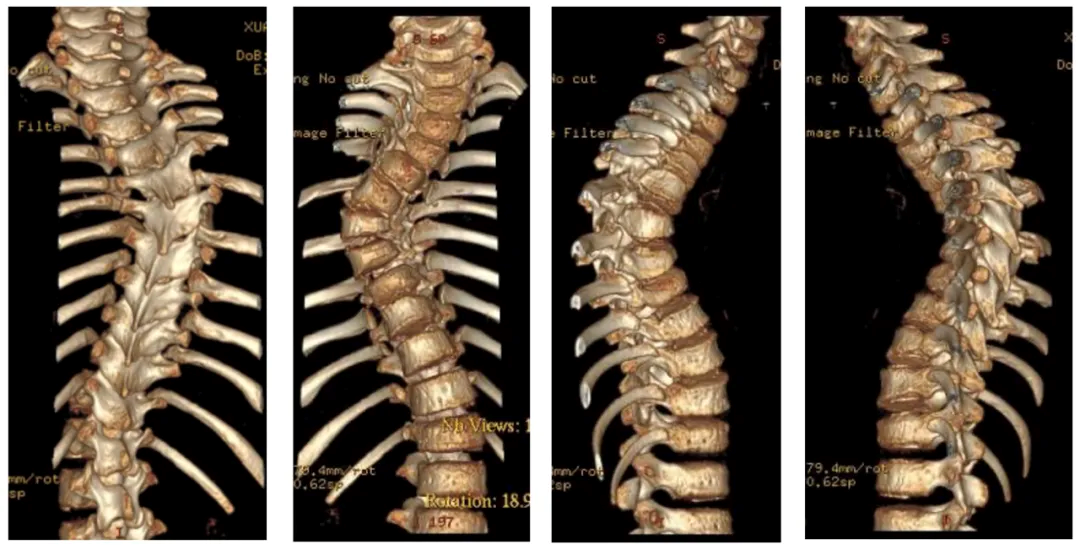

3. CT of thoracic spine showing scoliosis

(3) O-arm fluoroscopy was used to implant bilateral pedicle screws at T9 and T12-L3, right pedicle screw at T7, and new pedicle screws at T2-3 and T10-11, but the remaining pedicles were not able to be implanted due to dysplasia;

(4) Fluoroscopy showed satisfactory screw position and temporary rod fixation. Ultrasonic bone knife was used to remove the T12-L3 vertebral plate and inferior articular process. The upper rod is slightly compressed on the left side and slightly braced on the right side;